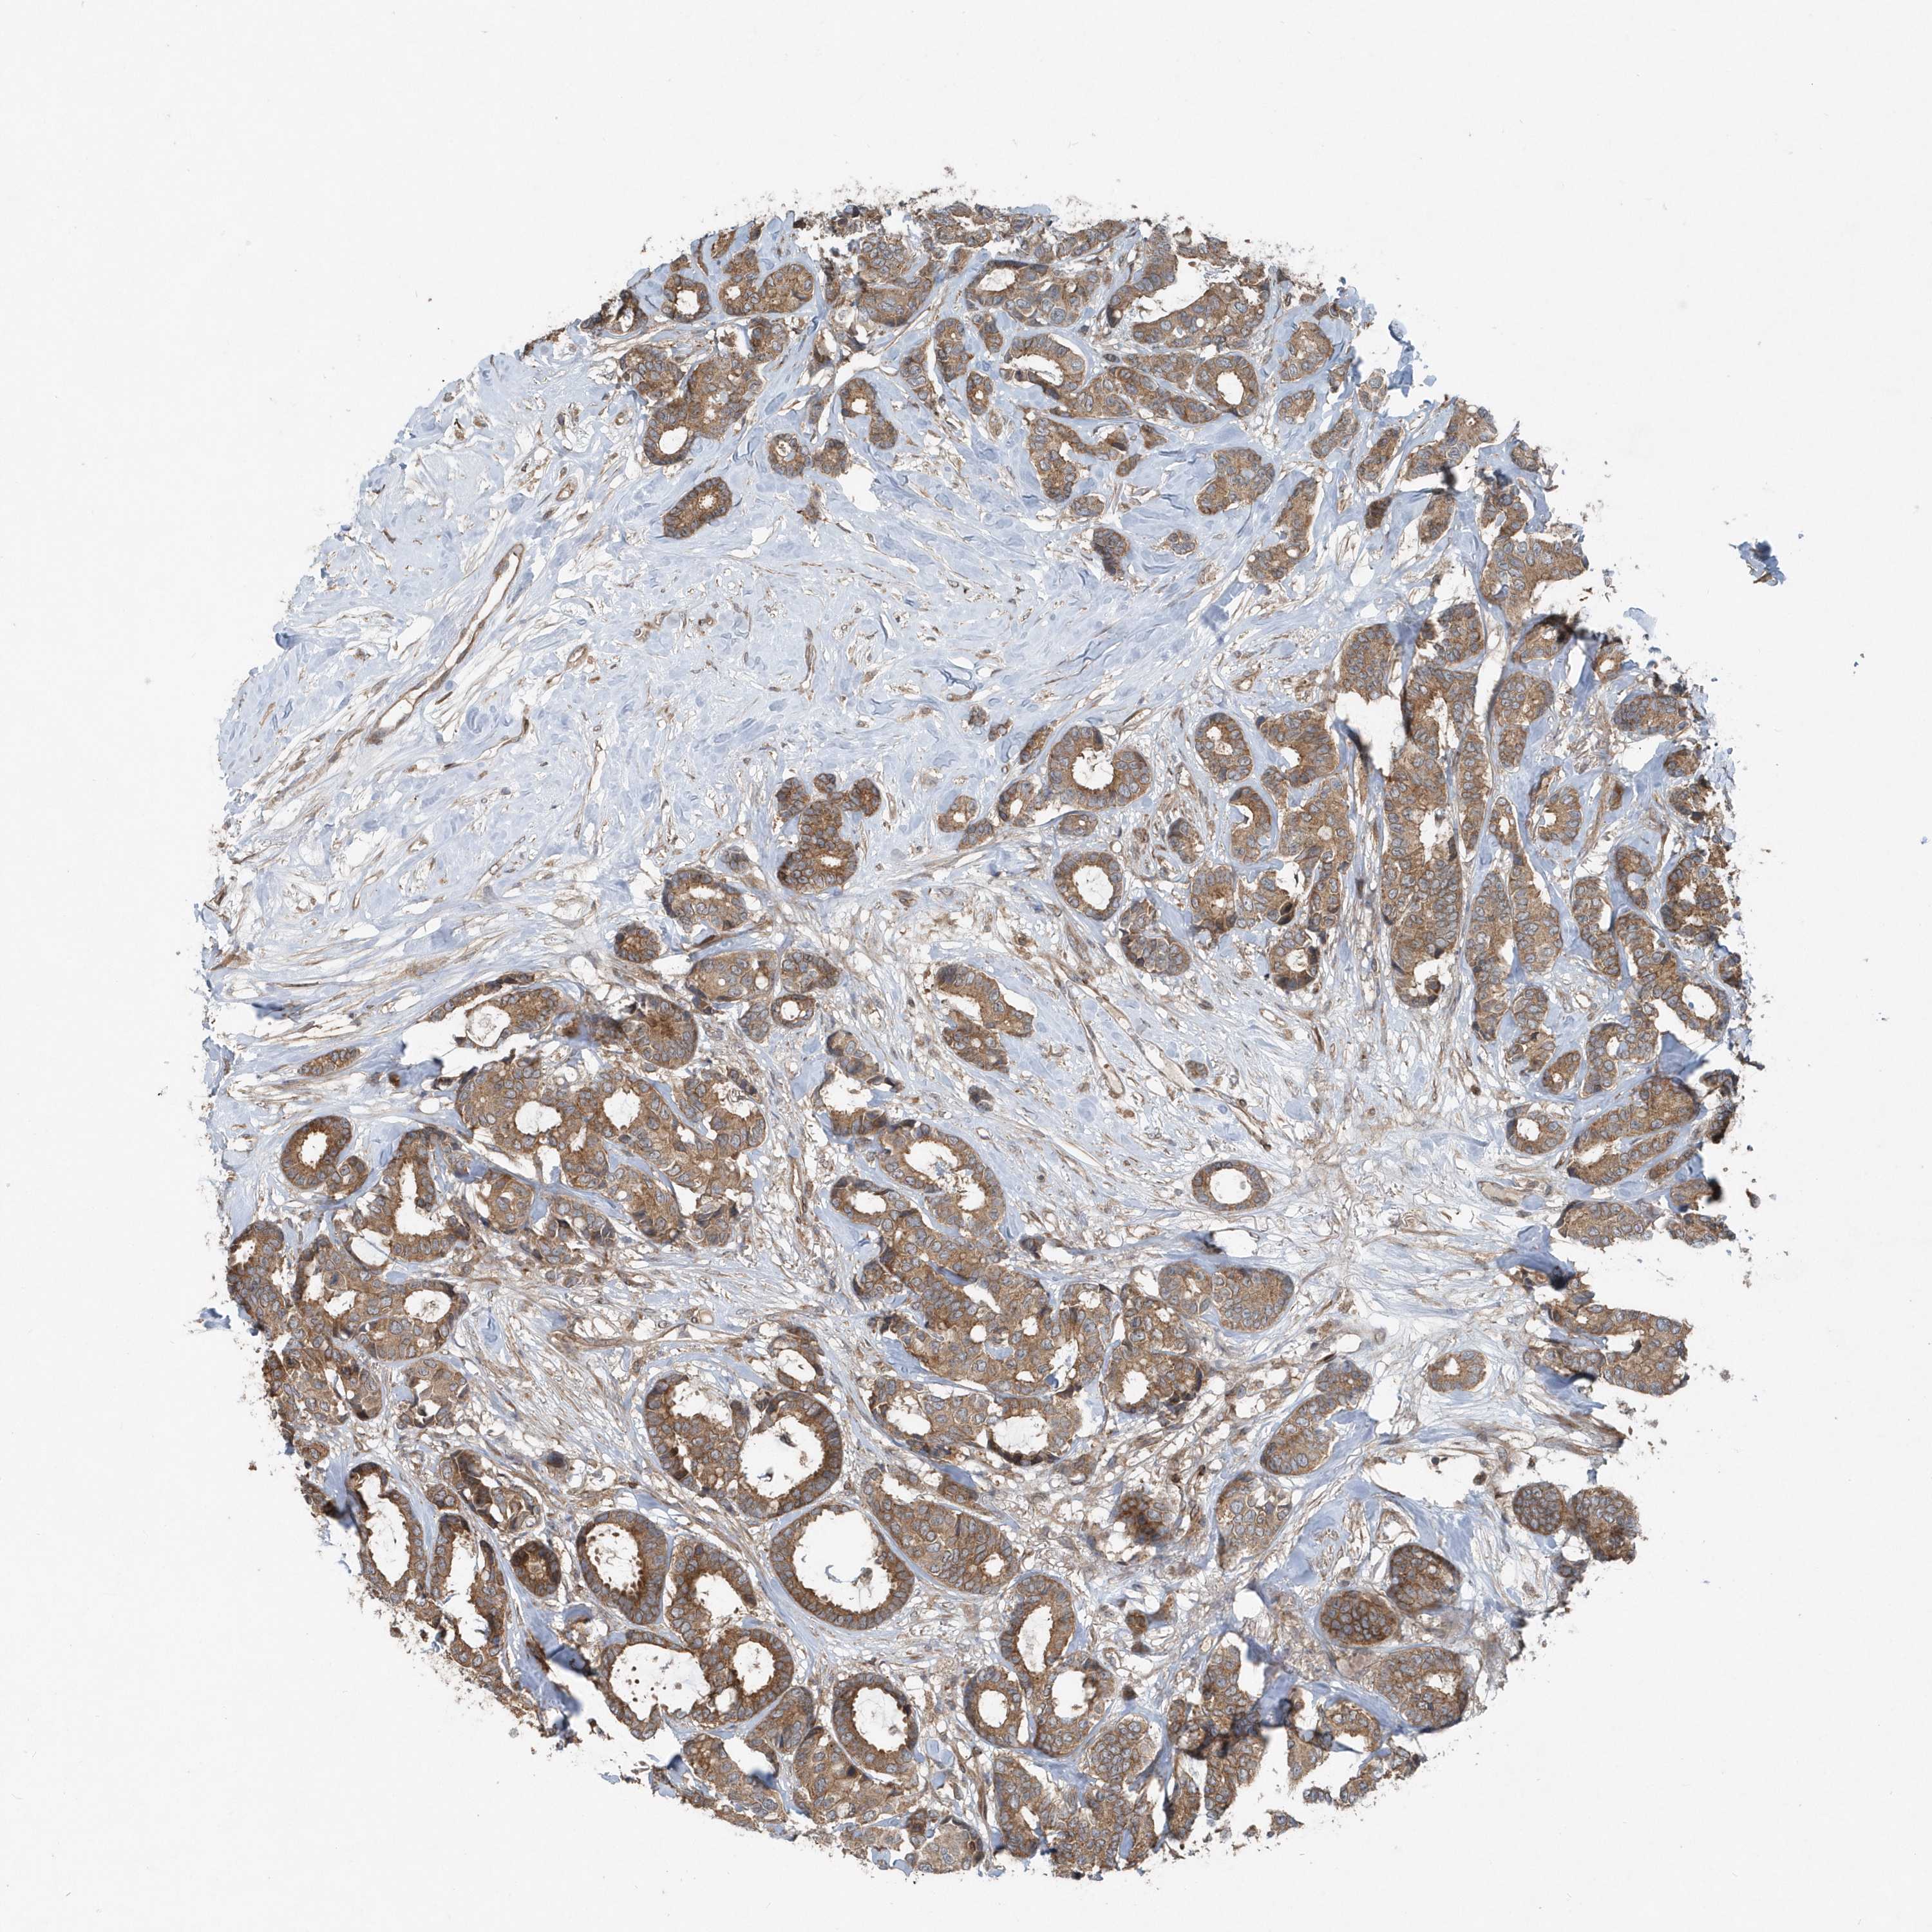

CANCER BREAST CANCER Show tissue menu

BRCA TCGA BRCA VALIDATION PROTEIN EXPRESSION